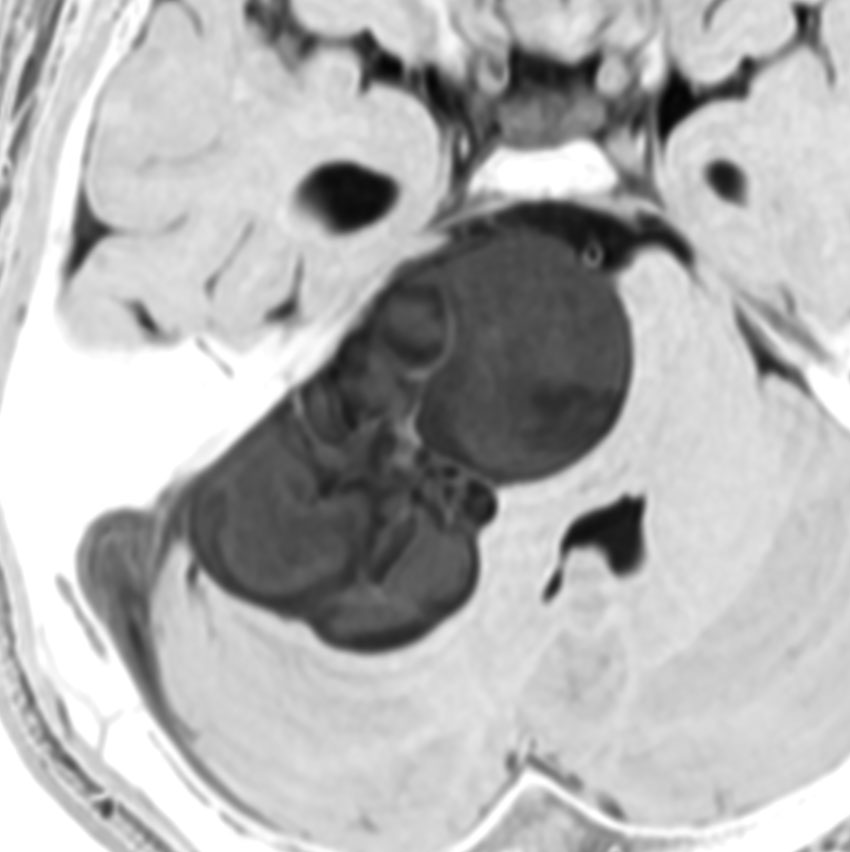

聴神経腫瘍や三叉神経鞘腫と間違えそうな顔面神経鞘腫

20代の男性で,下顎と口腔内の軽度の感覚以上だけがありました。聴力は正常で顔面神経麻痺は全くありません。でもこれは巨大な顔面神経鞘腫です。手術前は三叉神経鞘腫を疑っていました。

内耳道が少し拡大して内耳道内にも腫瘍があります。

手術摘出しましたが,聴神経は正常に見えて手術後も聴力は保たれました。三叉神経からは完全に剥離できています。

腫瘍の外側表面で顔面神経は紙のように薄くなって(菲薄化して),モニターで位置を確かめながらのかなり難しい手術となりました。